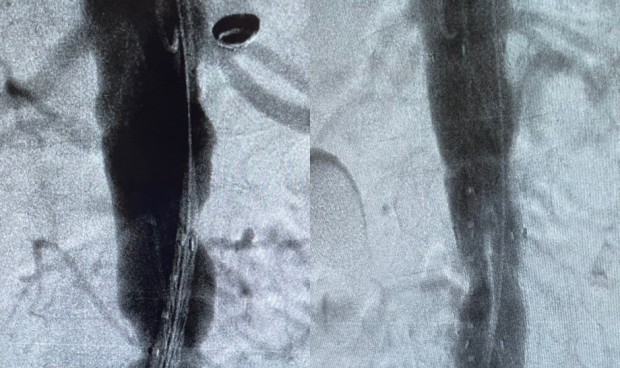

En este sentido, el facultativo de Quirónsalud Clideba destaca que “el resultado es la colocación de una endoprótesis aórtica casi a medida para ese paciente, de un tejido especial que permite aliviar la presión de sangre en la aorta inflamada para que no se rompa y baje la inflamación”. Así, la intervención se realiza a través de la arteria femoral, por un orificio de 6 milímetros y sin necesidad de heridas.

En cuanto a las ventajas que proporciona la intervención “para el paciente son todas. Resuelve un problema de riesgo vital sin heridas, con un ingreso de 72 horas, recuperando su vida normal a las 24 de la intervención y con la tranquilidad de que su caso es estudiado con la tecnología más avanzada existente y tratado por profesionales con más de 150 casos de este tipo intervenidos a sus espaldas”, concluye.